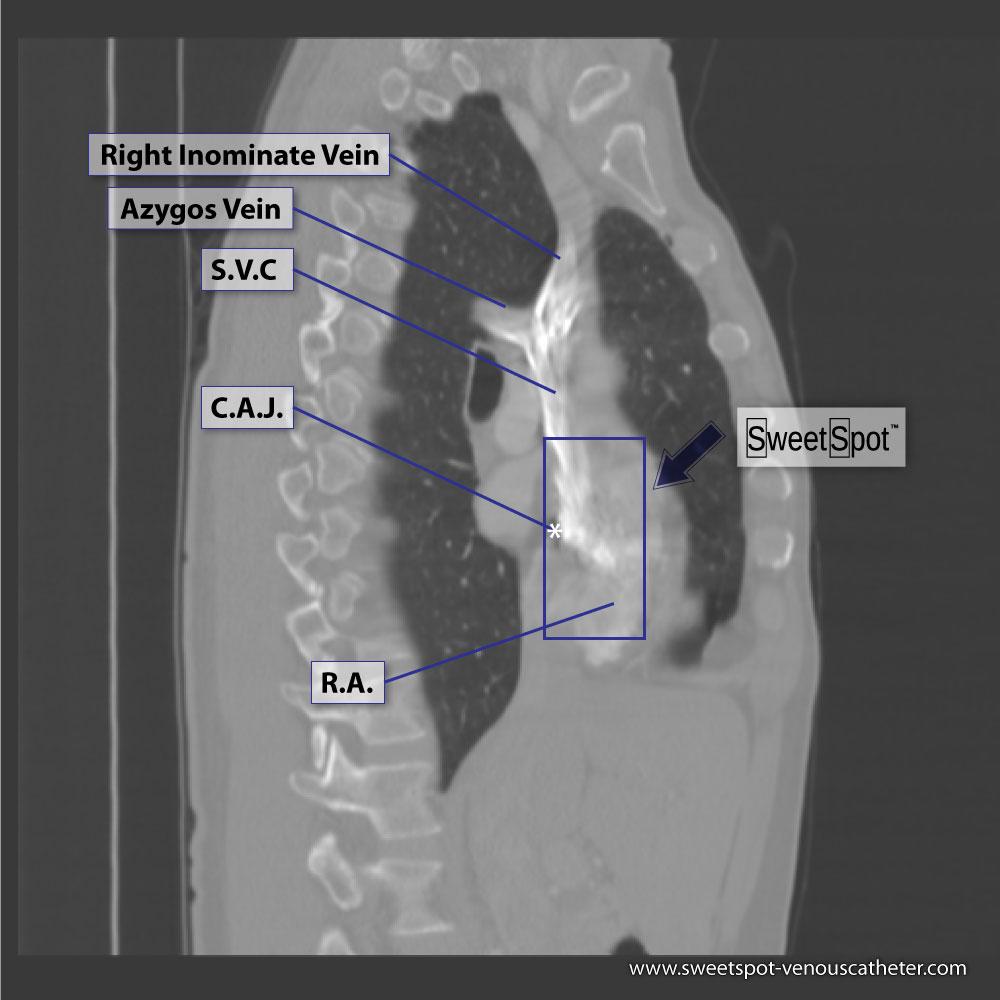

Sagittal CT reconstruction |

Figure - 17